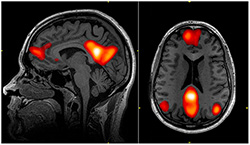

MRI is short for Magnetic Resonance Imaging. An MRI scanner takes pictures of your brain and creates 3D images. The images show your brain top to bottom and side to side. You will lie down in the MRI scanner, which is about the size of a play tunnel, while it takes pictures. It is safe, easy, and painless. The scanner is pretty noisy, so you will wear earbuds and headphones to block out the sound.

FMRI stands for functional magnetic resonance imaging. FMRI shows what your brain looks like while it’s thinking about something in particular, like a funny joke, or a difficult math problem. When a part of the brain is working hard, it needs more oxygen, just as your lungs need more oxygen when they’re working hard.

FMRI lets scientists see when a part of the brain uses more or less oxygen. When you do a math problem, for example, more oxygen flows to the parts of your brain that are working to solve the problem. If you do this while having an fMRI, scientists can see your brain “in action”. So fMRI helps scientists see which parts of the brain are important for thinking about different things. (Photo: John Graner, Walter Reed National Military Medical Center)